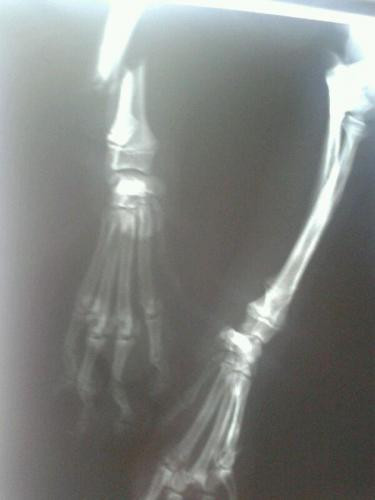

Airon tiña unha pata dianteira rota, e tamén os dedos da outra pata.

Xa está operado. agora se recupera a espera dun fogar.